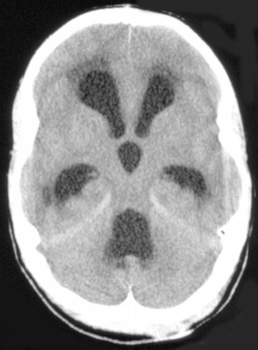

Hydrocephalus, a problem with the ratio of production of CSF to its reabsorbtion, is most frequent in children. Communicating hydrocephalus is the most common and is due to arachnoid villi and subarachnoid space obstruction. Obstructive hydrocephalus is less common but may occur as a result of the following:

![]() ![]() ![]() In these sections from the same patient notice the enlagement of the ventricles and cisterns that occurs with hydrocephalus. |